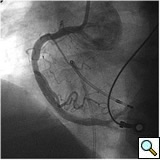

PCI of the vein and arterial grafts have unique challenges. For any PCI, guide support is very important for successful balloon and stent delivery. In a tortuous vein graft with a steep angle, advancement of a stent can be very difficult and challenging. Therefore, it is important to choose the best available catheter before starting PCI. Similar to the right coronary angiography, a JR4 guide catheter is most commonly used in this setting. However, Amplatz guide catheters for left vein grafts and multipurpose catheters for right vein grafts are better choices in certain anatomy. In Figure 8 and Figure 10 two examples of poor guide support in two vein graft interventions can be seen. Initially, a JR4 guide was used for PCI of the vein graft supplying the left anterior descending artery (LAD) without any success. However, after changing the guide to an Amplatz left 2 guide catheter, we achieved excellent support without any difficulty in advancing two stents (Figure 9). In Figure 10, difficulty is illustrated in engaging the vein graft ostium supplying the right coronary artery with a JR4 catheter. This vein graft has a very steep inferior take off from the aorta. After changing the guide to a multipurpose catheter, we were able to deliver three stents successfully without any difficulties (Figure 11). Similar challenges exist in the treatment of the left IMA or right IMA. These arterial grafts can be extremely tortuous making stent delivery very difficult. It may be necessary to use short length stents for a better deliverability or stents with lowest profile. Usually, similar to the native coronary intervention, a 6 French guide is appropriate for the routine use.